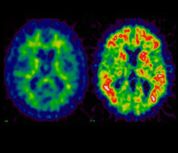

Positron Emission Tomography (PET)

The Siemens Biograph 6 PET/CT scanner features 6 slice CT, a multi-detector ring system and 3D reconstruction. An Allogg Automated Blood Sampling System (ABSS) is available for those studies which require arterial blood sampling; there is also an adjacent tissue/blood processing lab with dual-HPLC/radioactivity detectors for tracer metabolite analysis.